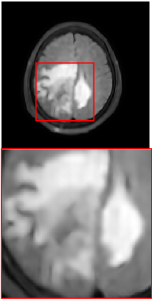

Figure 5 provides the qualitative comparison of the various methods on the four datasets at a scale of 4. The top, second, third, and bottom rows are the SR results under the FastMRI, clinical brain, clinical tumor and clinical pelvic datasets, respectively. The red boxes indicate the zoom-in region of complicated anatomical structures along with their corresponding error maps. Note that the brighter textures in the error maps, the lower the quality of the reconstructed images. As can be seen, compared to methods based on Transformers and CNNs, diffusion-based methods like DisC-Diff and DiffMSR (Ours) are capable of reconstructing high-realistic images with promising reconstruction metric scores (PSNR and SSIM). Nevertheless, while DisC-Diff can reconstruct high-precision MR images, it does not preserve the structure present in the original HR images, introducing some additional information that can affect medical diagnosis. In contrast, our method combines DM and PLWformer, which can preserve the original image’s structure while restoring high-frequency information.